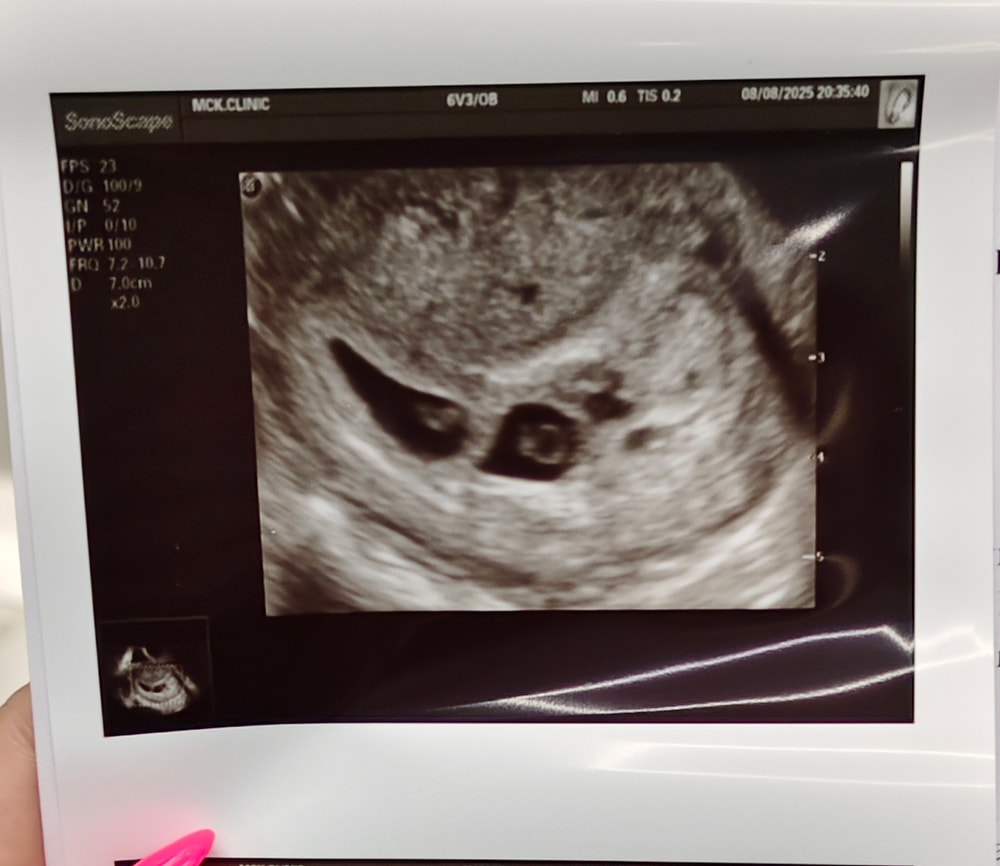

Вот это новость! Поздравляю вас! 🎉 Вы знаете, я ничего не понимаю в УЗИ, но когда я увидела ваше первое УЗИ в 5 недель, я подумала (перед тем как прочитать ваш пост), что у вас двойня, потому что там затемнения были в двух местах 😄😄😄

Юлия, спасибо огромное, мы все увидели, но врач решила не радовать раньше времени) вот уже оба сердечка послушали🥰

Урааа!:) мои поздравления! Не очень разбираюсь по узи, у Вас 1 плодное яйцо, а в нем два малыша? Или 2 яйца?

Helen, по фотке 2 пя вроде, если каждый в своем домике 😍

Helen, спасибо, два отдельно)